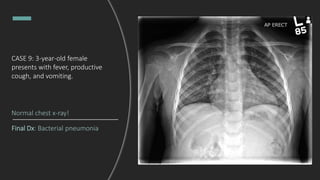

CASE 9: 3-year-old female

presents with fever, productive

cough, and vomiting.

Interpret this chest X-ray.

Right upper lobe pneumonia with

tracheal deviation towards the area of

consolidation. Per the radiology read,

ddx includes bacterial pneumonia or

post-obstructive pneumonia.

Given concerns for post-obstructive

pneumonia, a repeat chest x-ray was

obtained two weeks later to

evaluate for underlying mass.

What do you see?

Final Dx: Bacterial pneumonia

Normal chest x-ray!